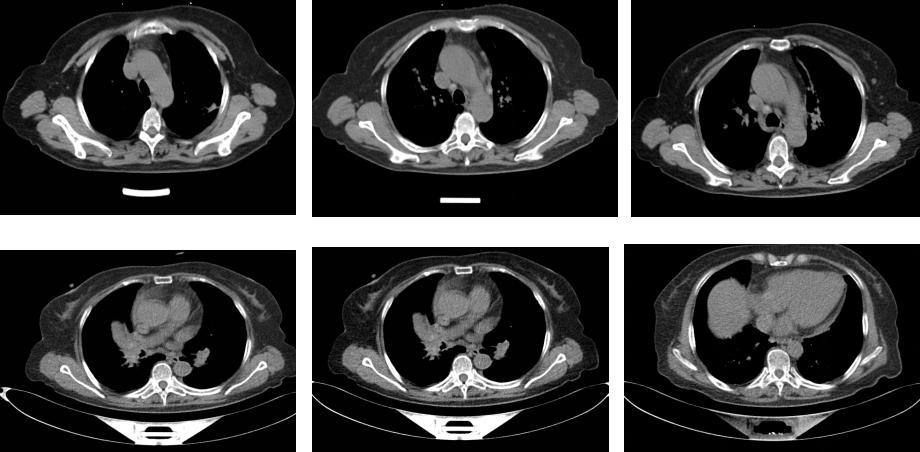

复查胸部CT:双肺以肺门为中心多发结节,支气管纹理粗乱,支气管血管束增粗,支气管肥厚狭窄,纵膈淋巴结增大,部分淋巴结钙化(图8)。

图8:第三次CT